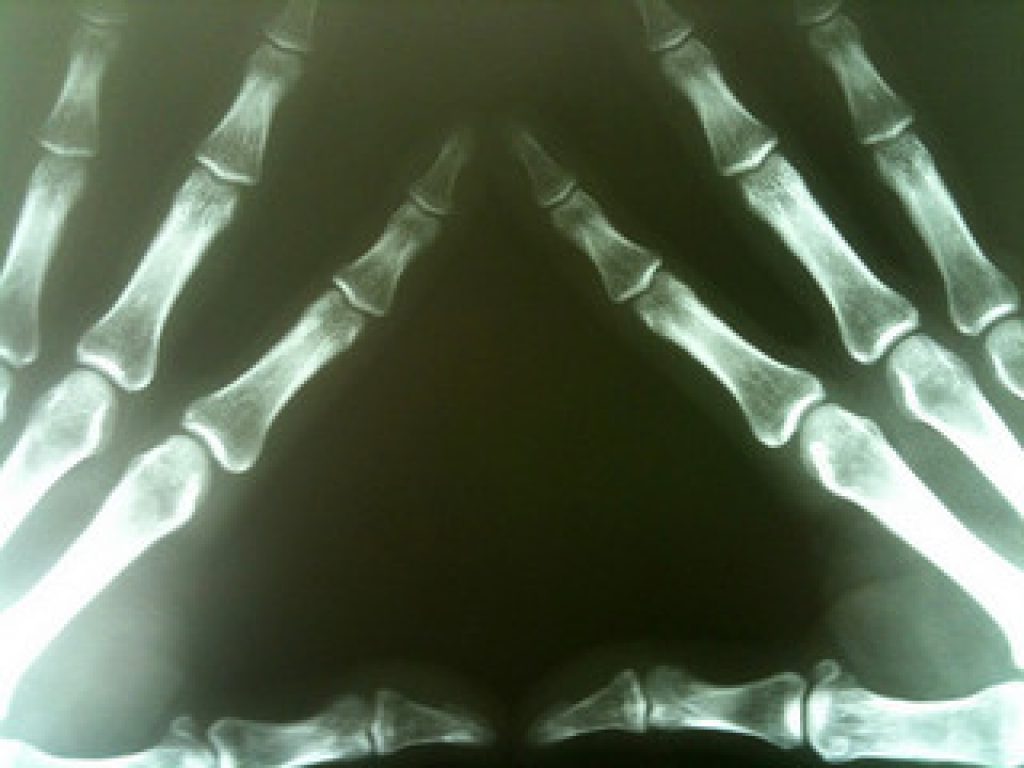

Childhood, or juvenile, arthritis can be a physically debilitating and emotionally challenging condition as those affected may be unable to perform even simple tasks because of joint swelling. Many children with arthritis also suffer from life-long psychological effects.

In their study, the researchers looked at 115 children with juvenile arthritis. Early results from the study showed that changes in the levels of particular molecules known as prostanoids in the blood of these patients may predict the course of arthritis more accurately.